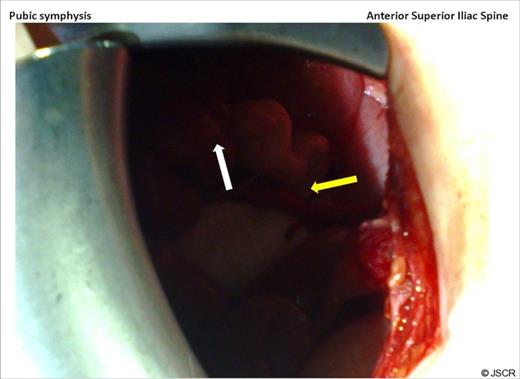

Amyand’s hernia is difficult to diagnose clinically and is rarely diagnosed preoperatively. In a review of 60 cases over a 12 year period only one case was diagnosed pre operatively (7). The difficulty in diagnosis has its origins in the considerable variation of symptoms that patients present with, depending on if the appendix is normal, incarcerated or perforated with the commonest presenting symptom being painful inguinal or inguinoscrotal swelling while the history and examination usually point to an incarcerated hernia (8). Fever and leukocytosis are inconsistent findings. Preoperative CT has revealed the previously unsuspected diagnosis in an occasional report and is useful in establishing the diagnosis early but is not routinely used in clinical situations where a complicated hernia is suspected. Laermann et al illustrated that combining CT with Multi Planar Reconstruction is the most useful technique, to better visualise the appendix and its relationship with surrounding structures, thus aiding in confidently making the correct diagnosis pre-operatively (6). In our case, the appendix could not be visualised, given that the patient has bilateral hip prosthesis, which produced artefact at the level of the appendix. (Figure 4.)

Artefact on CT, secondary to bilateral hip prosthesis, which obscures the appendix.